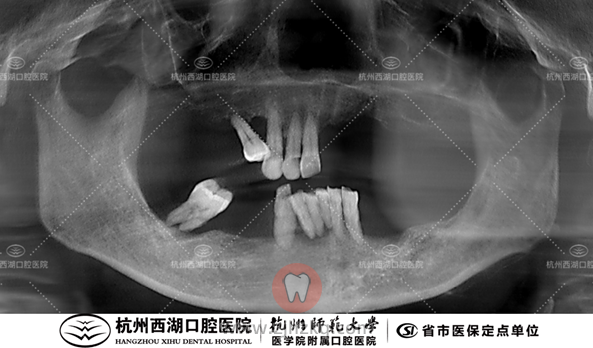

术前CBCT照如下

术后CBCT照如下